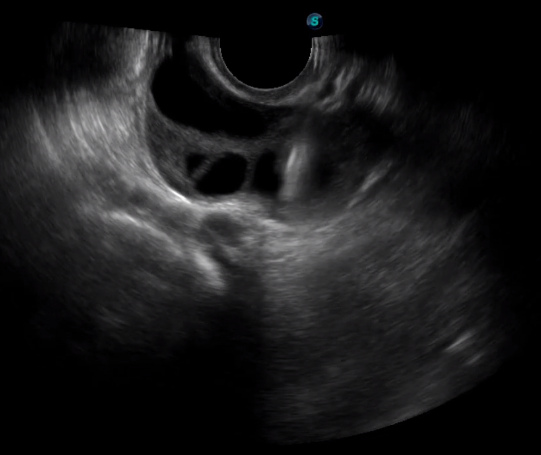

2宮腔專用探頭

多數(shù)的生殖科醫(yī)生對于受精卵的植入采用憑經(jīng)驗操作或是使用傳統(tǒng)腔內(nèi)探頭引導,同樣存在手術(shù)空間小、受精卵放置位置不確定等風險。專業(yè)的宮腔專用探頭,配合專用的窺器使用,為醫(yī)生提供最大的手術(shù)視野。

胎移植臨床圖